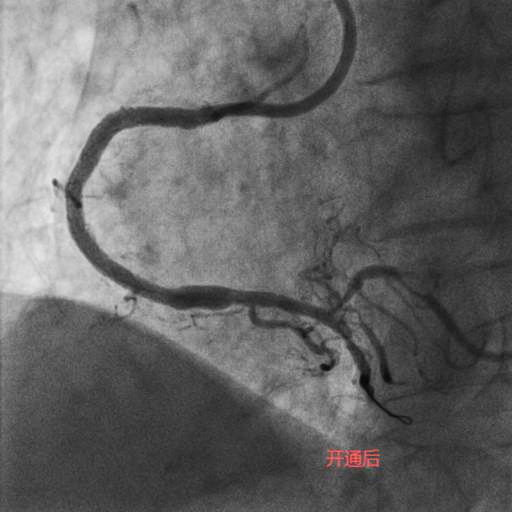

李奶奶今年92岁高龄,两年前曾因“急性心肌梗死”就诊于某医院,接诊专家考虑患者年龄大,合并症多,冠状动脉介入操作风险高,建议药物治疗。近半个月,李奶奶的胸痛症状频繁发作,药物治疗效果不佳,经过病友的介绍,家属选择了潞河医院翟光耀主任团队。在心脏监护室医护人员的精心治疗和护理下,李奶奶心功能改善,肺部感染得到控制,可以耐受手术。术中,冠状动脉造影显示LAD弥漫重度狭窄,RCA完全闭塞伴重度钙化。在经过近两个小时的不断尝试及努力后,闭塞的RCA成功开通,“介入无植入”未植入支架,血管成功修复。术后李奶奶恢复良好,顺利出院。